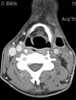

Neck infection